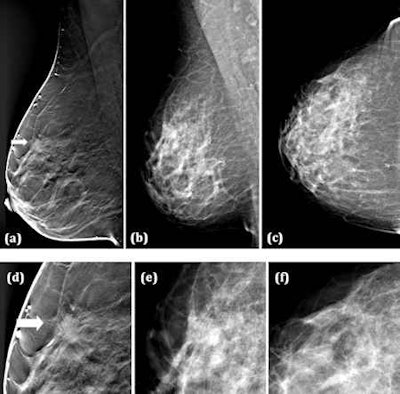

"Two views -- mediolateral oblique and craniocaudal -- can partially compensate for the overlapping anatomical noise [produced by digital mammography], but this depends on the radiologist's ability to mentally fuse the two images," Svahn and colleagues wrote in the British Journal of Radiology (6 June 2012). "Breast tomosynthesis collects two-dimensional projection views over a limited angular range, which allows reconstruction of thin slices of the breast volume."

Svahn's team compared radiologists' ability to detect breast cancers using two-view digital mammography and one-view breast tomosynthesis (Mammomat Novation DR and a tomosynthesis prototype based on this device, both Siemens Healthcare). The prototype breast tomosynthesis system delivered about the same average glandular dose as the two-view digital mammography system, they noted.